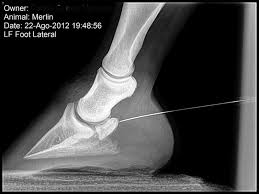

Fractura abierta

Otra de las fracturas en caballos que forman parte de esta lista es la fractura abierta, en esta la piel se abre dejando el hueso roto expuesto y visible, por otro lado se encuentran las fracturas cerradas, en esta la piel sigue intacta y recubre la zona afectada del hueso.